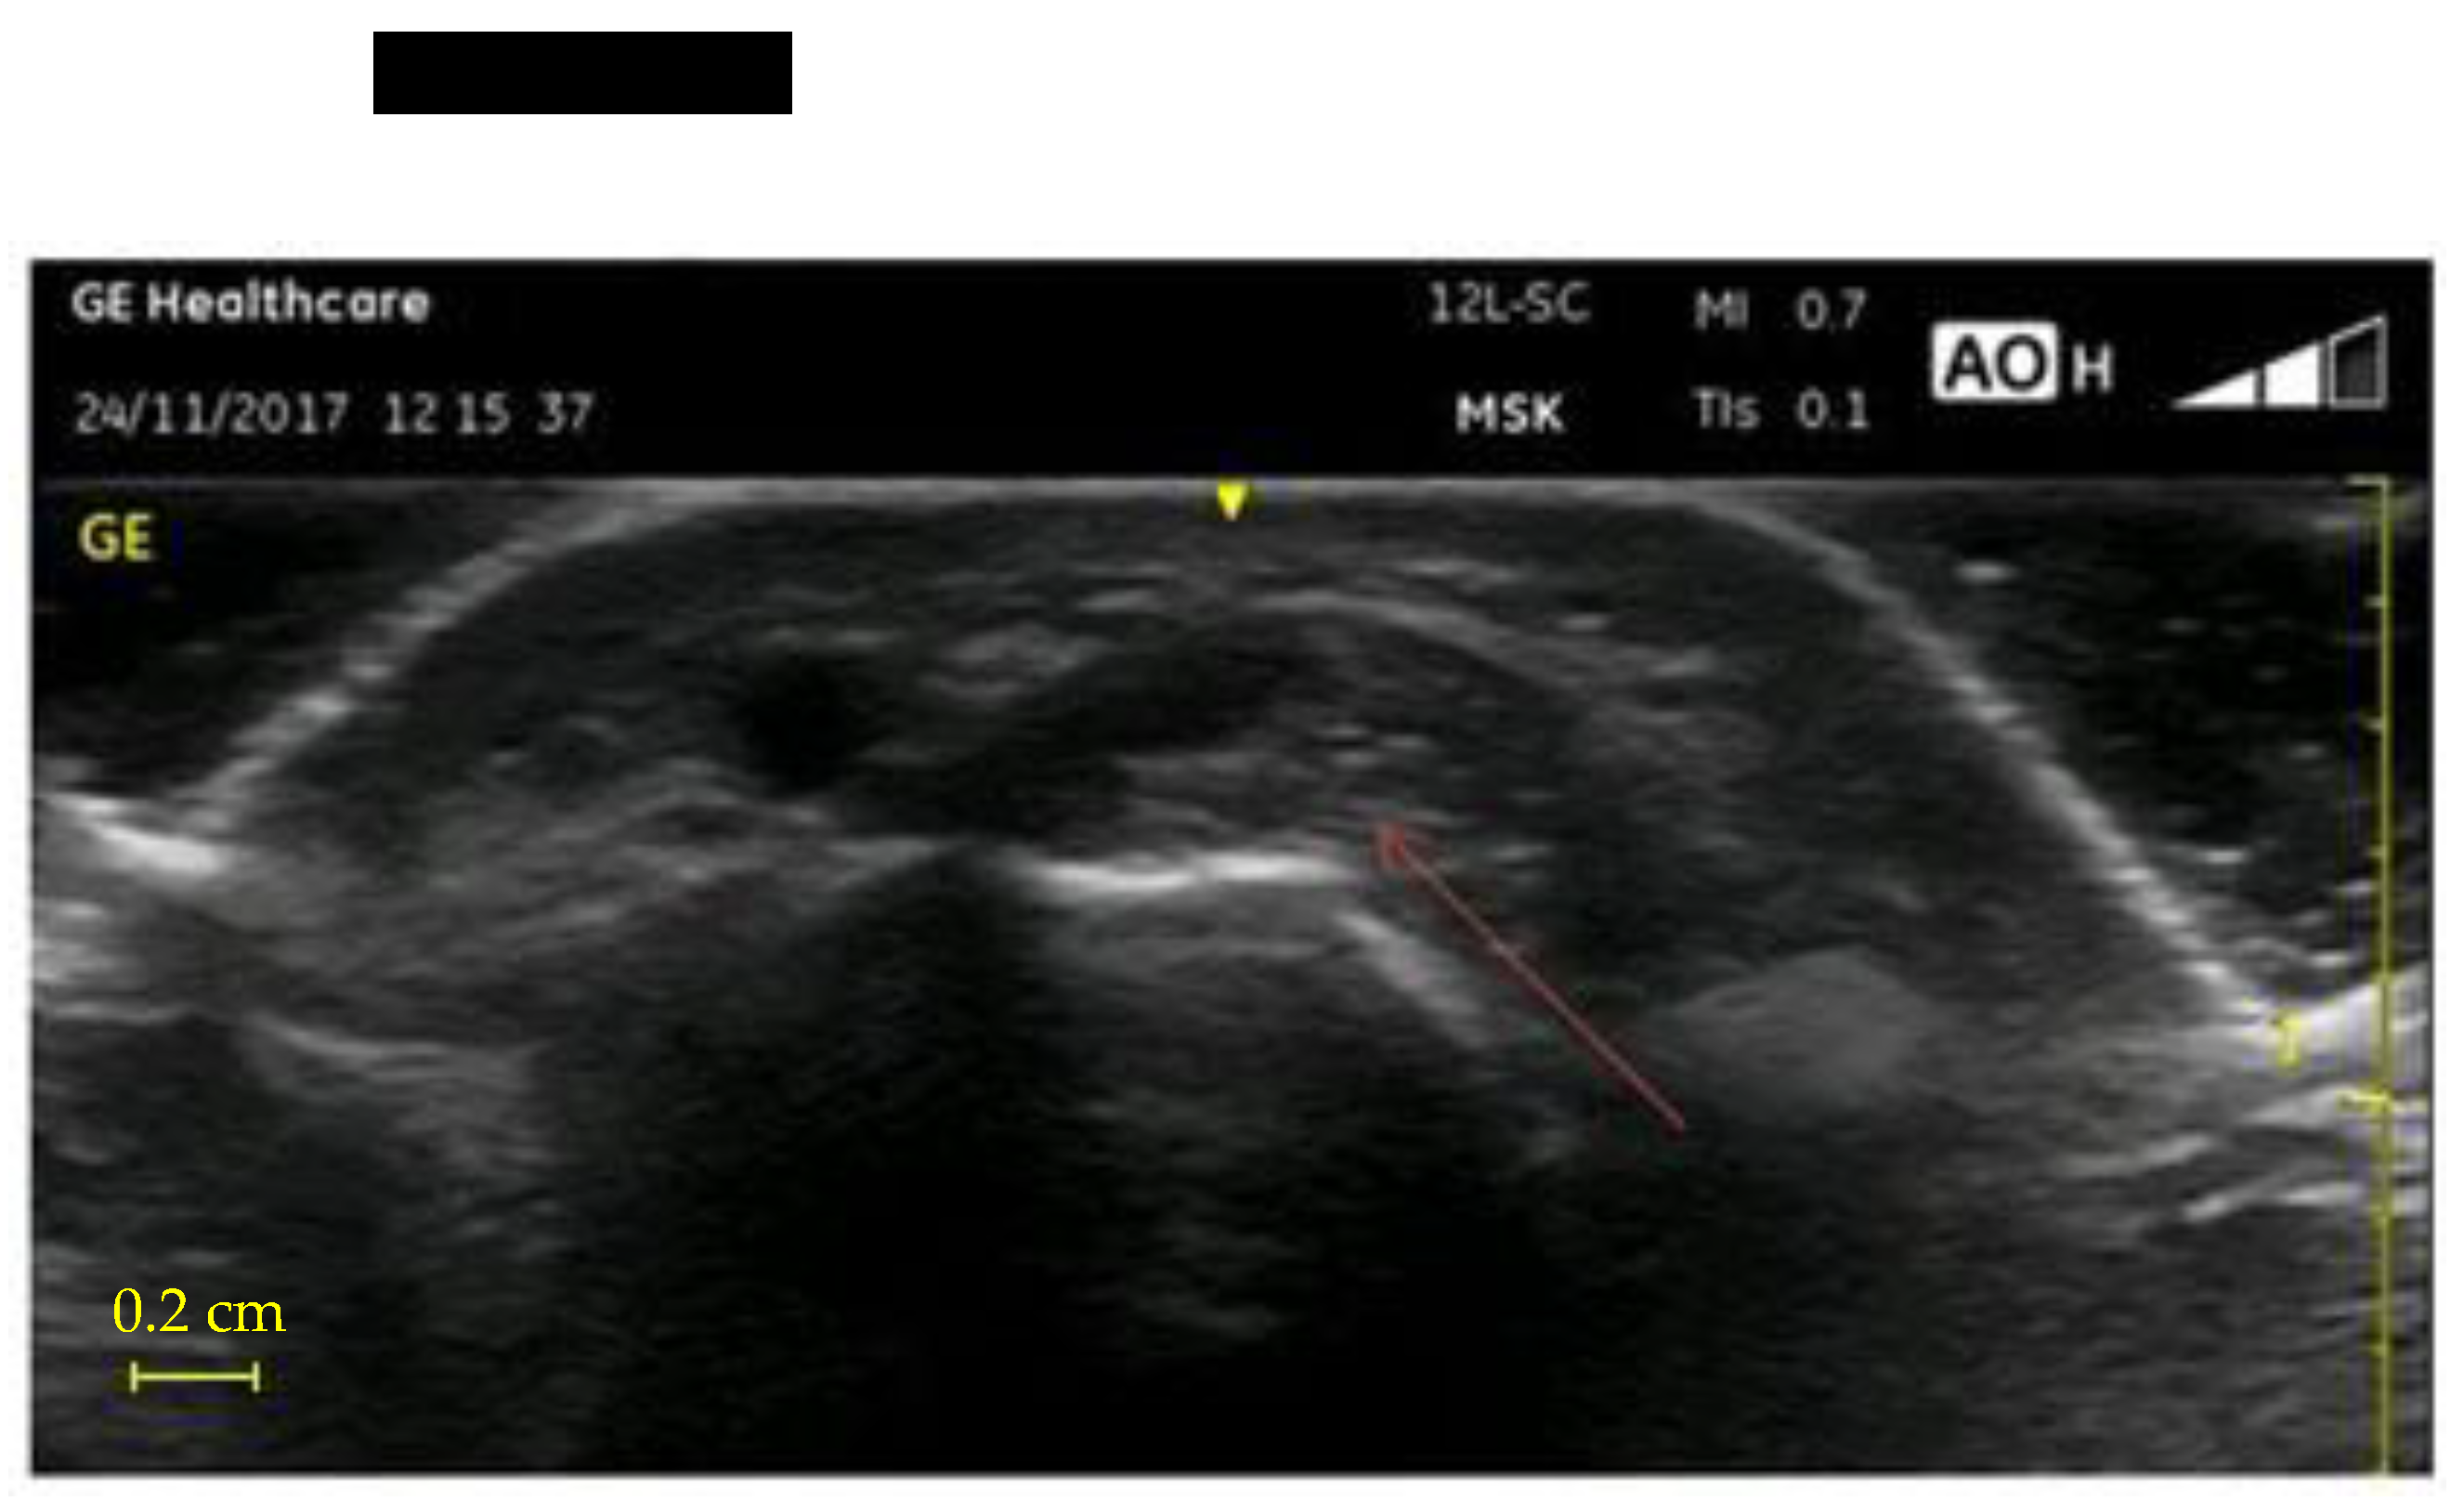

- UI of the hand-wrist area, performed with portable ultrasound device (Venue Scan, Venue 40, GE Healthcare®, Chicago, IL, USA) that allowed the researchers to store the examinations for further evaluation and discussion with other hospital experts in the final evaluation of all cases. A trained sonographer performed the wrist ultrasound. According to the European Society of Musculoskeletal Radiology’s protocol (ESSR) [23], acoustic windows were investigated in both the dorsal wrist, focusing on the extensor tendons and the radiocarpal joint, and the ventral wrist, focusing on the flexor tendons and the median nerve (Table 1).